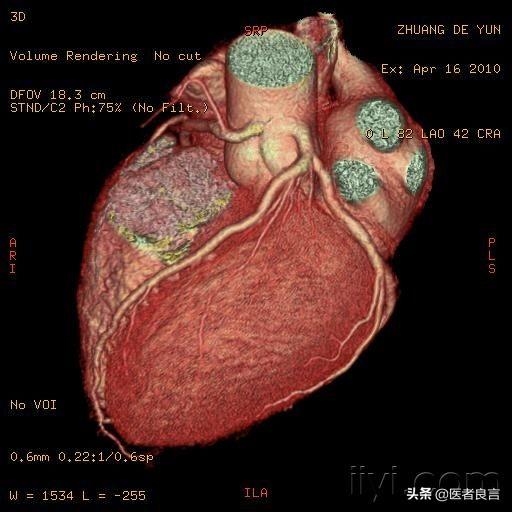

例を挙げよう:

冠動脈疾患の診断は、30ドルの心電図検査であったり、4,000ドルの画像診断であったりする。心臓画像診断は冠動脈疾患診断のゴールドスタンダードではあるが、冠動脈疾患を診断するためにすべての人に行うことを意図しているわけではない。

冠動脈疾患の診断には、症状、危険因子、心電図、時には血圧と外来心電図、運動負荷試験、冠動脈CTA、冠動脈造影などがある。

出血、血腫、巻き込み、腎毒性、アレルギーなどのリスクを伴う侵襲的な検査である画像診断を行わなくても、症状と30ピースの心電図だけで冠動脈疾患を診断できることもある。

良心的な原則とは、「使用できるものは単純で、複雑ではない」「使用できるものは非侵襲的で、侵襲的ではない」「使用できるものは安価で、高価ではない」というものである!